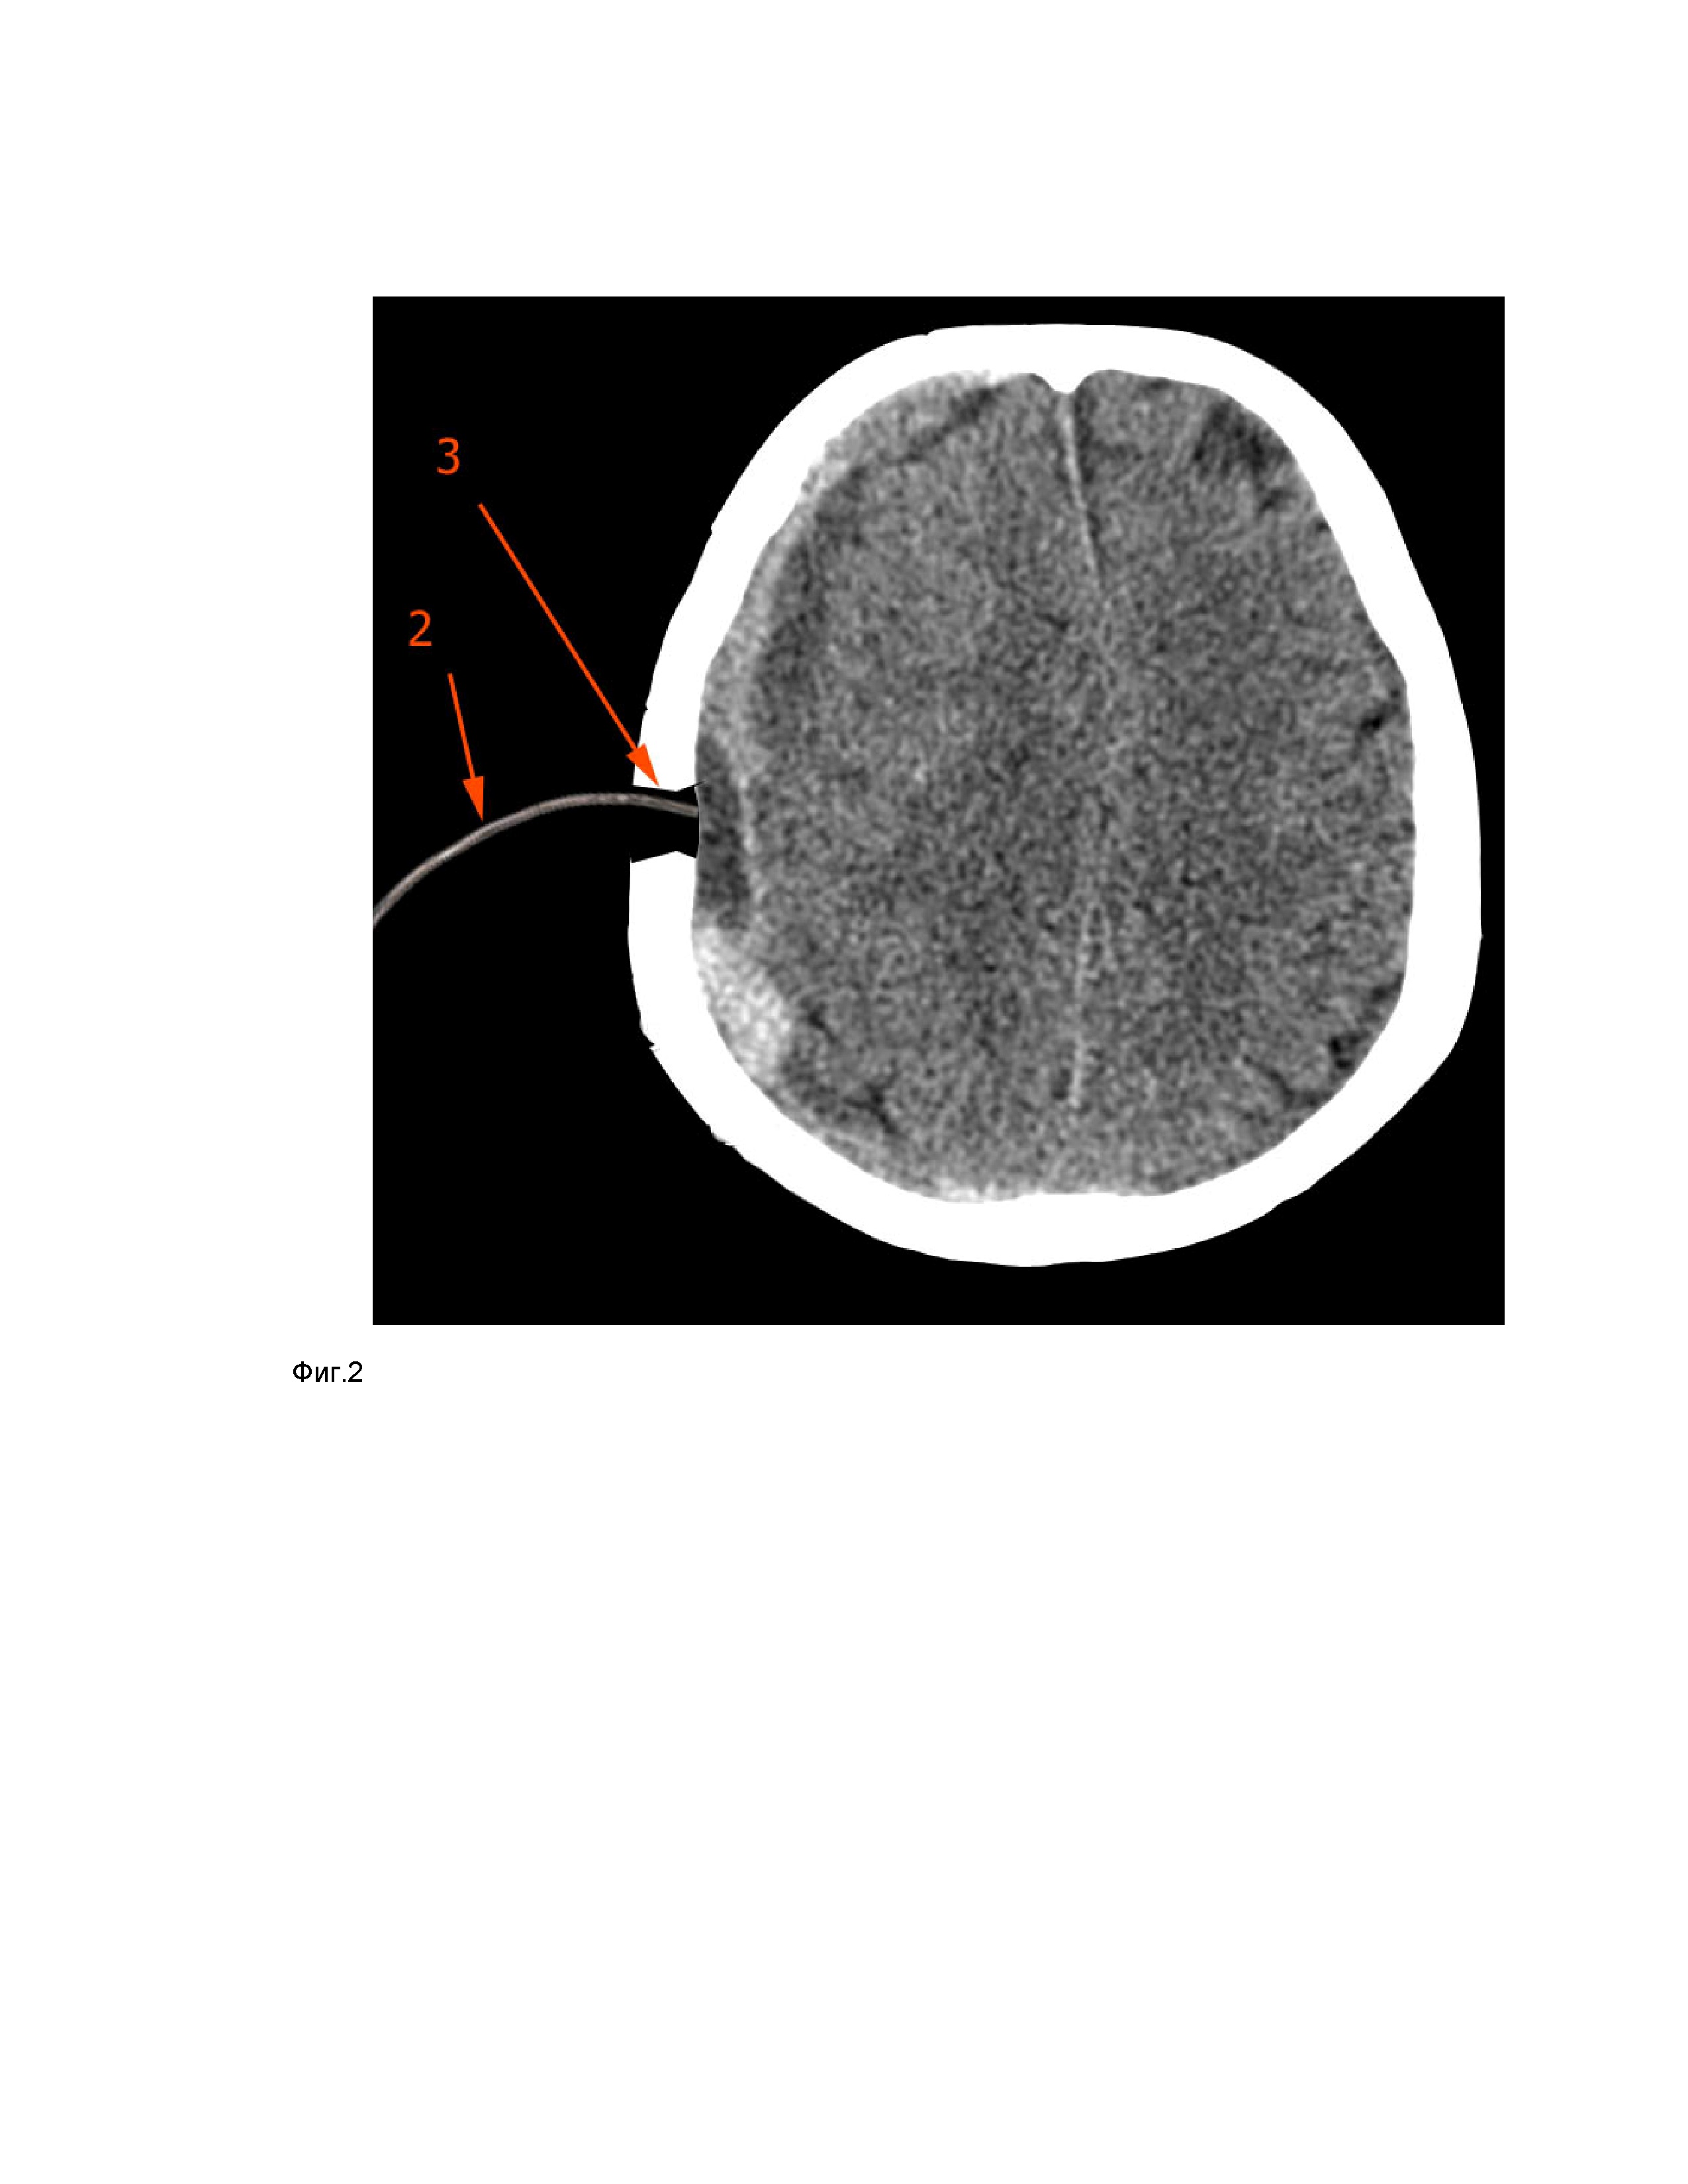

Указанные результаты в предлагаемом способе оперативного лечения субдуральных гематом достигается использованием жесткого эндоскопа с углом обзора 450 или 700. Такие эндоскопы широко распространены, производятся большинством производителей и используются в нейрохирургии и травматологии при целом ряде оперативных вмешательств. Пример расположения подострой субдуральной гематомы (1) показан на фиг.1. После обработки операционного поля выполняется разрез в проекции центра гематомы, длина его 3 см. Освобождается кость, фрезой накладывается отверстие в своде черепа диаметром менее 12 мм, при этом костная стружка сохраняется, временно удаляется из раны. Твердая мозговая оболочка вскрывается дугообразно, лоскут фиксируется швом. Если гематома имеет сформированную капсулу, она также вскрывается. В области отверстия (3) гематома выделяется самопроизвольно либо удаляется в отсос (2), что показано на фиг.2. В случае удаления острых и подострых гематом мозг обычно быстро расправляется и полость в области отверстия может закрыться, однако большая часть гематомы при этом останется. Такая ситуация показана на фиг.3, где расправившийся мозг (4) закрыл полость и значительная часть гематомы (1) не удалена. Чтобы этого не происходило, в полость гематомы проводится байонетный шпатель (7) шириной 6 мм, который обеспечивает ретракцию мозга для создания полости, расположение его показано на фиг.4, фиг.5. В случае удаления хронической гематомы мозг быстро не расправляется и установка шпателя не требуется. В отверстие вводится ригидный эндоскоп диаметром 4 мм с оптикой 45 градусов либо 700. Эндоскоп (6) устанавливается в отверстии под углом 450 (для эндоскопа 450) или 300 (для оптики 700), что обеспечивает обзор полости гематомы. Взаимное расположение шпателя (7), эндоскопа (6) и отсоса (2) показано на фиг.4. За счет угловой оптики обеспечивается хорошая визуализация полости без необходимости глубокого введения эндоскопа, что обеспечивает безопасность вмешательства. Эндоскоп является наименее контролируемым инструментом, так как хирург не видит его. Если использовать эндоскоп с меньшим углом обзора, то его будет необходимо горизонтально вводить под кость, что связано с риском повреждения вещества мозга и поломкой эндоскопа в узком отверстии. После обеспечения визуализации в полость вводится отсос и удаляется видимая при данном положении эндоскопа часть гематомы. Гематома удаляется отсосом, имеющим прогрессивный изгиб - прямой у основания и с радиусом на конце 50 мм, наружным диаметром до 4 мм. Трубка отсоса может быть изогнута дополнительно непосредственно во время вмешательства. Отсос вводится через фрезевое отверстие параллельно эндоскопу и ширины отверстия хватает для перемещения трубки отсоса в полости гематомы в пределах обзора. Введение отсоса рядом с эндоскопом, а не через рабочий канал, позволяет использовать больший диаметр трубки, при этом удаляются не только жидкая часть гематомы, но и сгустки. Все движения отсоса в полости производятся строго под визуальным контролем. Каждый раз удаляется сектор гематомы около 30 градусов, после чего шпатель и эндоскоп переставляется в следующий сектор гематомы. Последовательность удаления секторов гематомы показана на фиг.6. Пример результата удаления гематомы показан на фиг.7. Перегородки, обычные для хронических гематом, легко разрушаются отсосом. При обнаружении источника кровотечения выполняется гемостаз монополярной либо биполярной коагуляцией, а также обычными гемостатическими материалами. При удалении эпидуральной гематомы, расположенной поверх твердой мозговой оболочки оперативное вмешательство выполняется подобным образом без вскрытия твердой мозговой оболочки. После удаления эпидуральной гематомы твердая мозговая оболочка может подтягиваться швом в области отверстия для предотвращения рецидива гематомы. После удаления гематомы в полость под контролем эндоскопа устанавливается трубчатый дренаж, который проводится под апоневрозом и выводится на кожу в 3-5 см от раны. Лоскут твердой мозговой оболочки фиксируется швами, фрезевое отверстие закрывается сохраненной костной стружкой. Дренаж удаляется через 1-2 суток после операции.